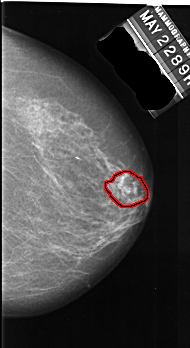

A_1015_1.RIGHT_MLO

RIGHT_MLO LINES 6256 PIXELS_PER_LINE 3046 BITS_PER_PIXEL 16 RESOLUTION 42 OVERLAY

FILE: A_1015_1.RIGHT_MLO.OVERLAY

TOTAL_ABNORMALITIES 1

ABNORMALITY 1

LESION_TYPE CALCIFICATION TYPE FINE_LINEAR_BRANCHING DISTRIBUTION LINEAR

ASSESSMENT 5

SUBTLETY 4

PATHOLOGY MALIGNANT

TOTAL_OUTLINES 1

BOUNDARY